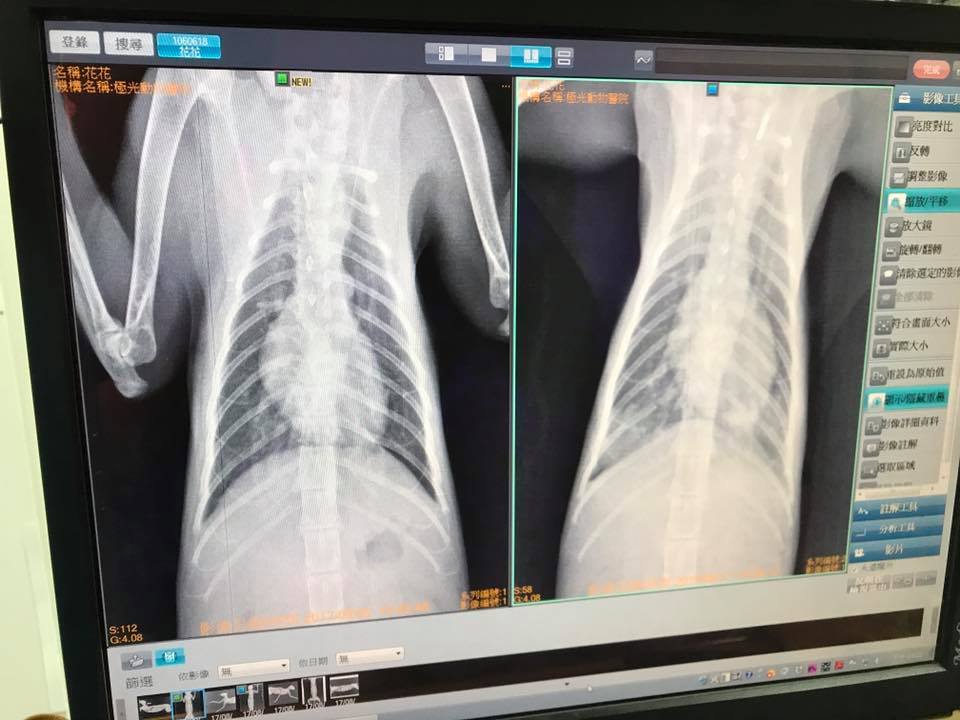

主題: 肺炎痊癒後仍有感染且呼吸急促的花媽 申請者姓名: 臺北市支持流浪貓絕育計劃協會 花色: 申請日期: 2017-09-25 11:29:47 申請者部落格: 申請者臉書網址: 所在縣市/合作醫院: 台北市/極光動物醫院 治療費用: 9570元 需求人數: 21人 已結案 (2024-06-01 13:21:47) 報名人員: vopoo x2(已付款)、Tracy Hsu x3(已付款)、Andy Hsu(已付款)、Melody Tsai x6(已付款)、Melody Tsai x9(已付款)、Caca Chang(已付款)、雲雲(已付款)、 候補人員: 動物病情說明: 住院時有肺炎及貧血,

住院時有肺炎,今X光檢查肺炎已經都好,所以白血球與發炎指數GLOB排除是肺炎造成的。